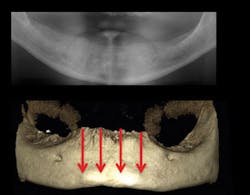

Figures 4-7: This series of images shows a clinical situation, the cone beam images, and the freehand implant placement.